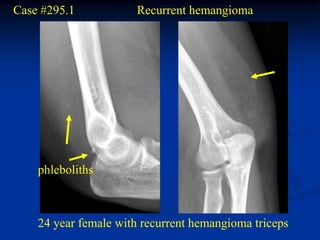

Case #295.1           Recurrent hemangioma

phleboliths

24 year female with recurrent hemangioma triceps

Case #295.1 Recurrent hemangioma phleboliths 24 year female with recurrent hemangioma triceps